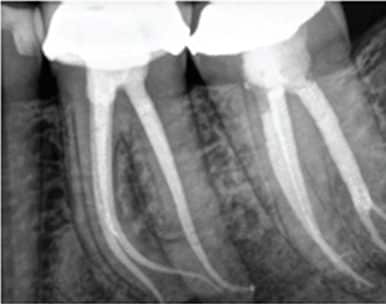

January 4, 2026 Service 0 Waa maxay dhuux daawayntu(Root Canal Treatment)? Dhuux daawayntu waa hab lagu daweeyo iligga marka uu suusku ama jabniinku gaadho dhuuxa ama neerfaha iligga kusoo jira. Sidoo kale kolka uu iliggu infection sameeyo.